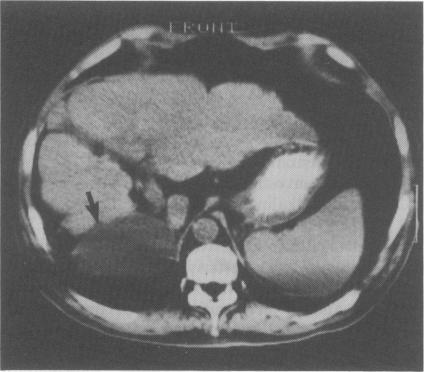

We describe a patient presenting with painless jaundice, anorexia and pruritus. The gall bladder was found to be lying above and behind a hypoplastic right lobe of liver. There was no evidence of cholangitis or biliary obstruction. The patient subsequently developed a bronchobiliary fistula with severe wheeze, cough and bile-stained sputum. Emergency percutaneous drainage of the gall bladder led to immediate cessation of bronchospasm and biloptysis, rendering the patient fit for definitive surgery.

我们描述了一位出现无痛性黄疸、厌食和瘙痒症状的患者。发现胆囊位于发育不全的肝右叶上方及后方。没有胆管炎或胆道梗阻的证据。该患者随后出现了支气管胆管瘘,伴有严重喘息、咳嗽和胆汁染色痰液。急诊经皮胆囊引流导致支气管痉挛和咯胆汁立即停止,使患者适合进行确定性手术。